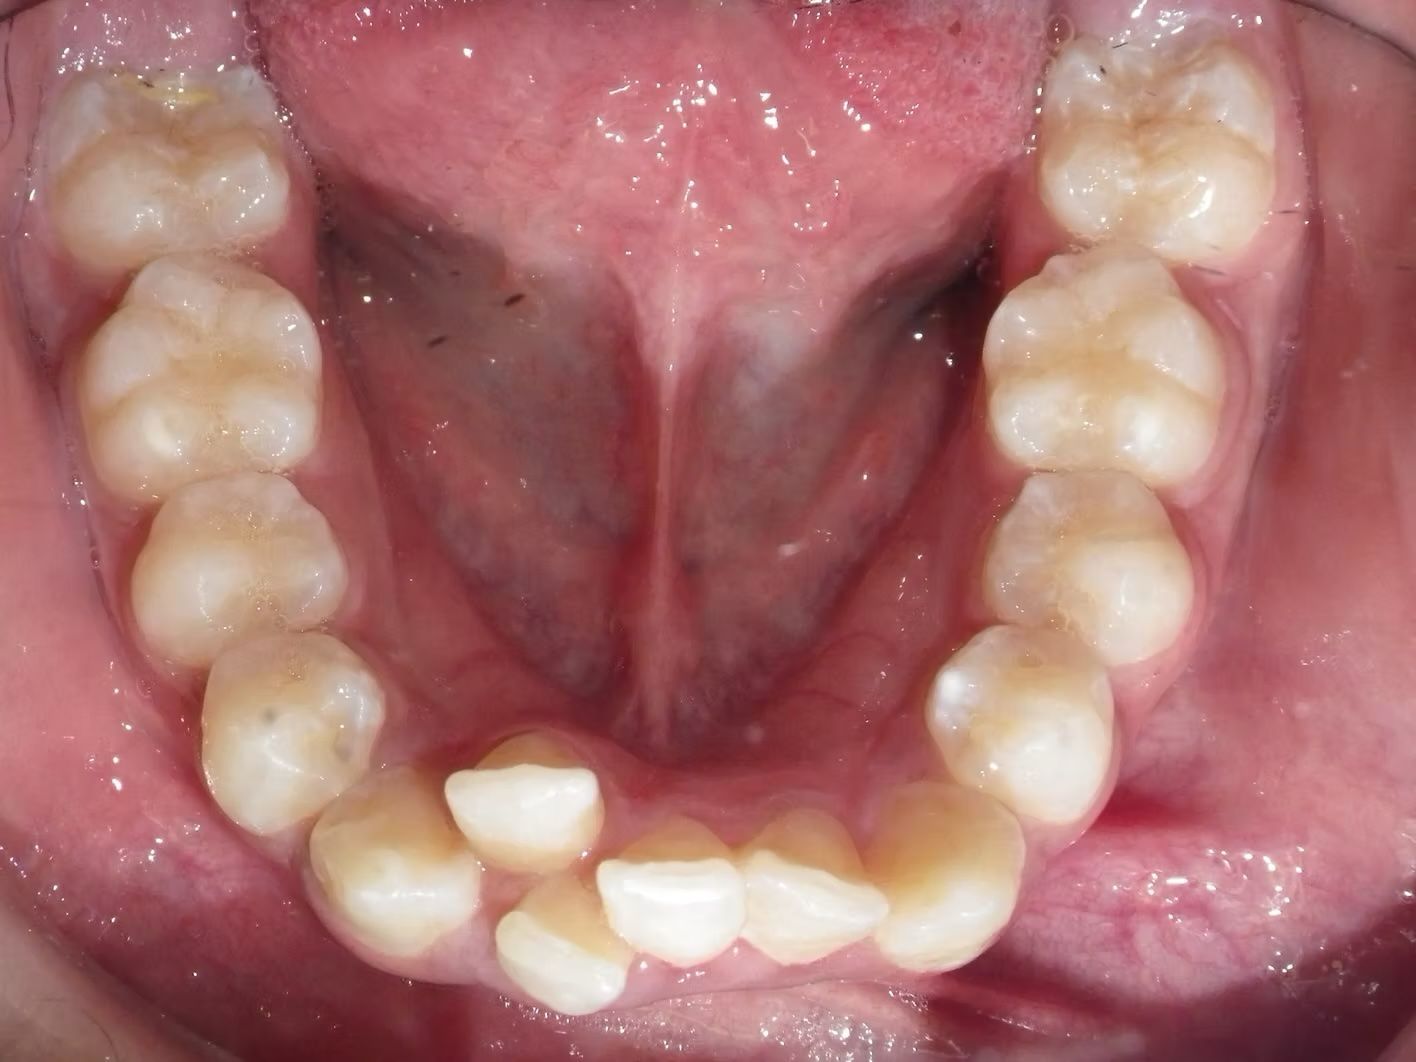

Johntavious

Johntavious didn't like that one of his lower teeth was set behind the rest. He went to many orthodontists who told him to extract the tooth or multiple teeth to correct the alignment. Johntavious and his parents didn't want to go that route and wanted to try to align the teeth without the extraction. Dr. Bret was able to successfully straighten the upper and lower teeth - fit the tooth that was back into the dental arch and make Johntavious and his parents really happy.